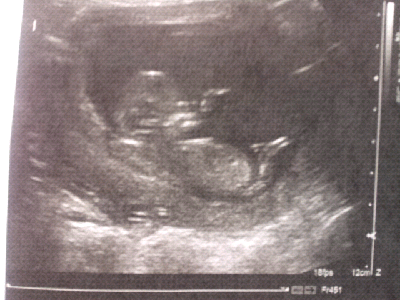

Finally announcing my pregnancy! Obviously my weight loss journey is on hold for the time being. Check or my new blog here :-)